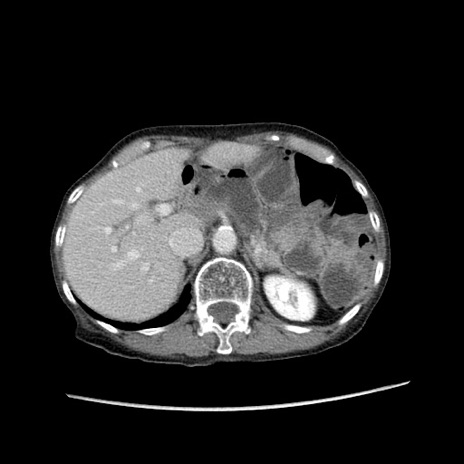

冠状断像

【症例】80歳代女性

【主訴】胸のつかえ感

【現病歴】約9時間前に食後から胸のつかえた感じあり、嘔吐あり、来院。

【既往歴】胃癌(全摘)、胆摘、虫垂炎

【身体所見】心窩部に圧痛あり、反跳痛なし。

【データ】WBC 5700、CRP 0.05